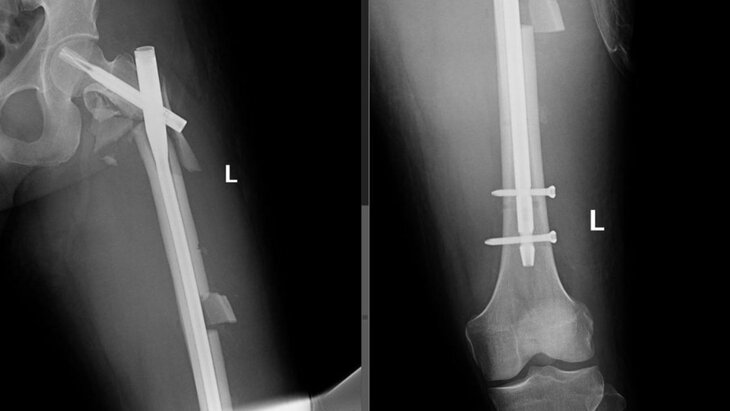

Пострадавший поступил в медучреждение с переломами позвонков, открытыми переломами ребра и костей левого предплечья, закрытыми переломами таза, левой бедренной кости с повреждением бедренной артерии, а также с другими травмами. Его предстояло прооперировать врачам разных профилей.

В результате медики смогли спасти ногу мужчины от ампутации, а также устранить последствия переломов и травм. Пациенту помогли в реабилитации и в скором времени выпишут.